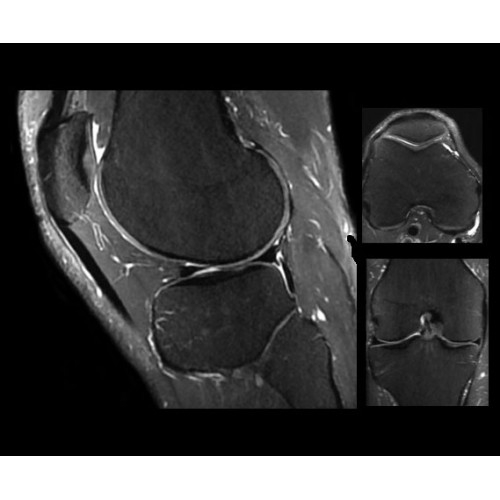

SIGNA PET/MR 3.0T — это гибридная система, в которой совмещаются две принципиально разные технологии — магнитно-резонансную томографию (МРТ) и позитронно-эмиссионную томографию (ПЭТ). Система отличающийся высокой чувствительностью и эффективностью и предназначена для диагностики в области онкологии, неврологии, кардио-васкулярных исследований, исследований воспалительных процессов.

Компания GE Healthcare представляет революционную, полностью интегрированную систему SIGNA PET/MR1, в которой сочетаются времяпролетная технология (TOF) и возможности напряженности магнитного поля 3.0 Тл. Мы поможем вам поднять исследования на более высокий уровень. SIGNA PET/MR позволяет достичь впечатляющей точности и скорости исследований, а благодаря новейшей технологии реконструкции Q.Clear2 качество изображений улучшается в два раза. Кроме того, в систему включен полный набор клинических приложений и гибких катушек для проведения любых видов исследования, открывая для вас возможности визуализации, о которых вы даже не догадывались.

Система SIGNA PET/MR предлагает впечатляющие клинические возможности и открывает доступ к наиболее полным пакетам программных приложений.

• Приложения для коррекции артефактов движения — используйте наиболее широкий набор инструментов, таких как PROPELLER, PROMO и навигаторы Pencil Beam, позволяющих снизить влияние непроизвольных или физиологических движений на качество изображений.

Стандартный пакет приложений SIGNA Works позволит вам достичь желаемых результатов в клинической практике благодаря набору высокоэффективных средств визуализации. Программные приложения, входящие в состав данных клинических пакетов, включают широкий спектр контрастов, функции обработки 2D- и 3D-данных, а также возможность коррекции артефактов движения. SIGNA Works предоставляет набор инструментов, необходимых для проведения эффективного клинического исследования.